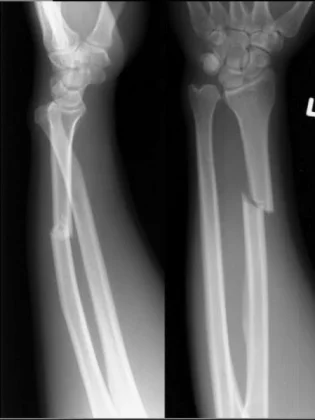

Forearm Fractures

- (Considered as a joint)

- Management:

- Undisplaced:

- Possible conservative - cast & follow up

- Displaced:

- Anatomical Open reduction and internal fixation by Plating and screws( best fixation)

- Early motion - Prevents stiffness